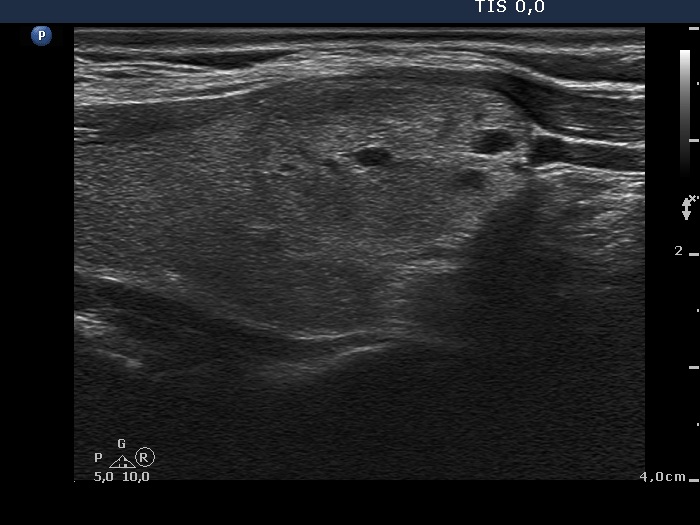

Ethanol sclerotherapy: non-toxic solid nodules - Case 5

Twelve years after the therapy (ultrasonographic picture 2)

Right lobe, longitudinal scan.